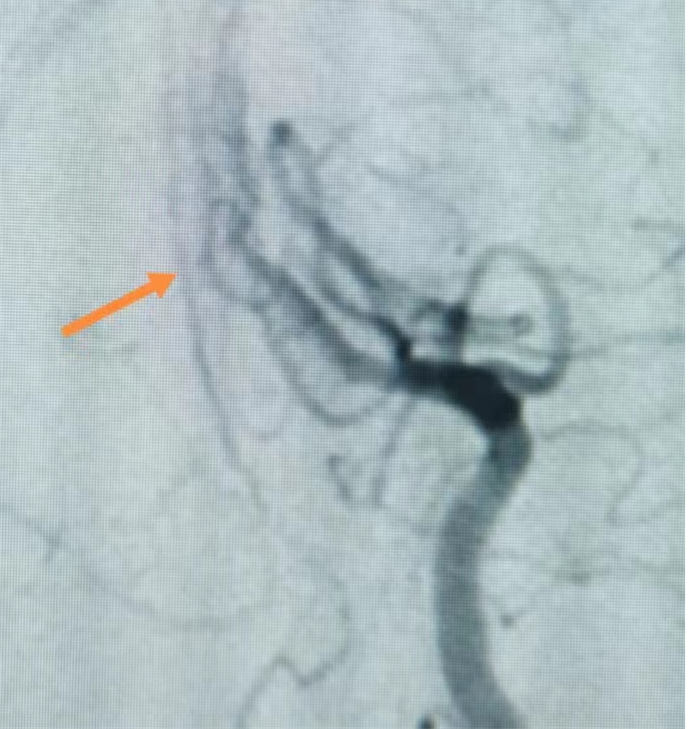

上圖為DSA造影

5月23日,經(jīng)過充分術(shù)前評(píng)估及準(zhǔn)備,在科主任袁玉麟積極協(xié)調(diào),介入導(dǎo)管室、麻醉與圍術(shù)期醫(yī)學(xué)科多科協(xié)作下,進(jìn)行了經(jīng)全麻下全腦血管造影+基底動(dòng)脈球囊擴(kuò)張術(shù)。手術(shù)歷時(shí)約30分鐘,術(shù)中順利。術(shù)后予輸液、對(duì)癥治療。術(shù)后第2天,患者即能下床活動(dòng);術(shù)后第4天順利出院。